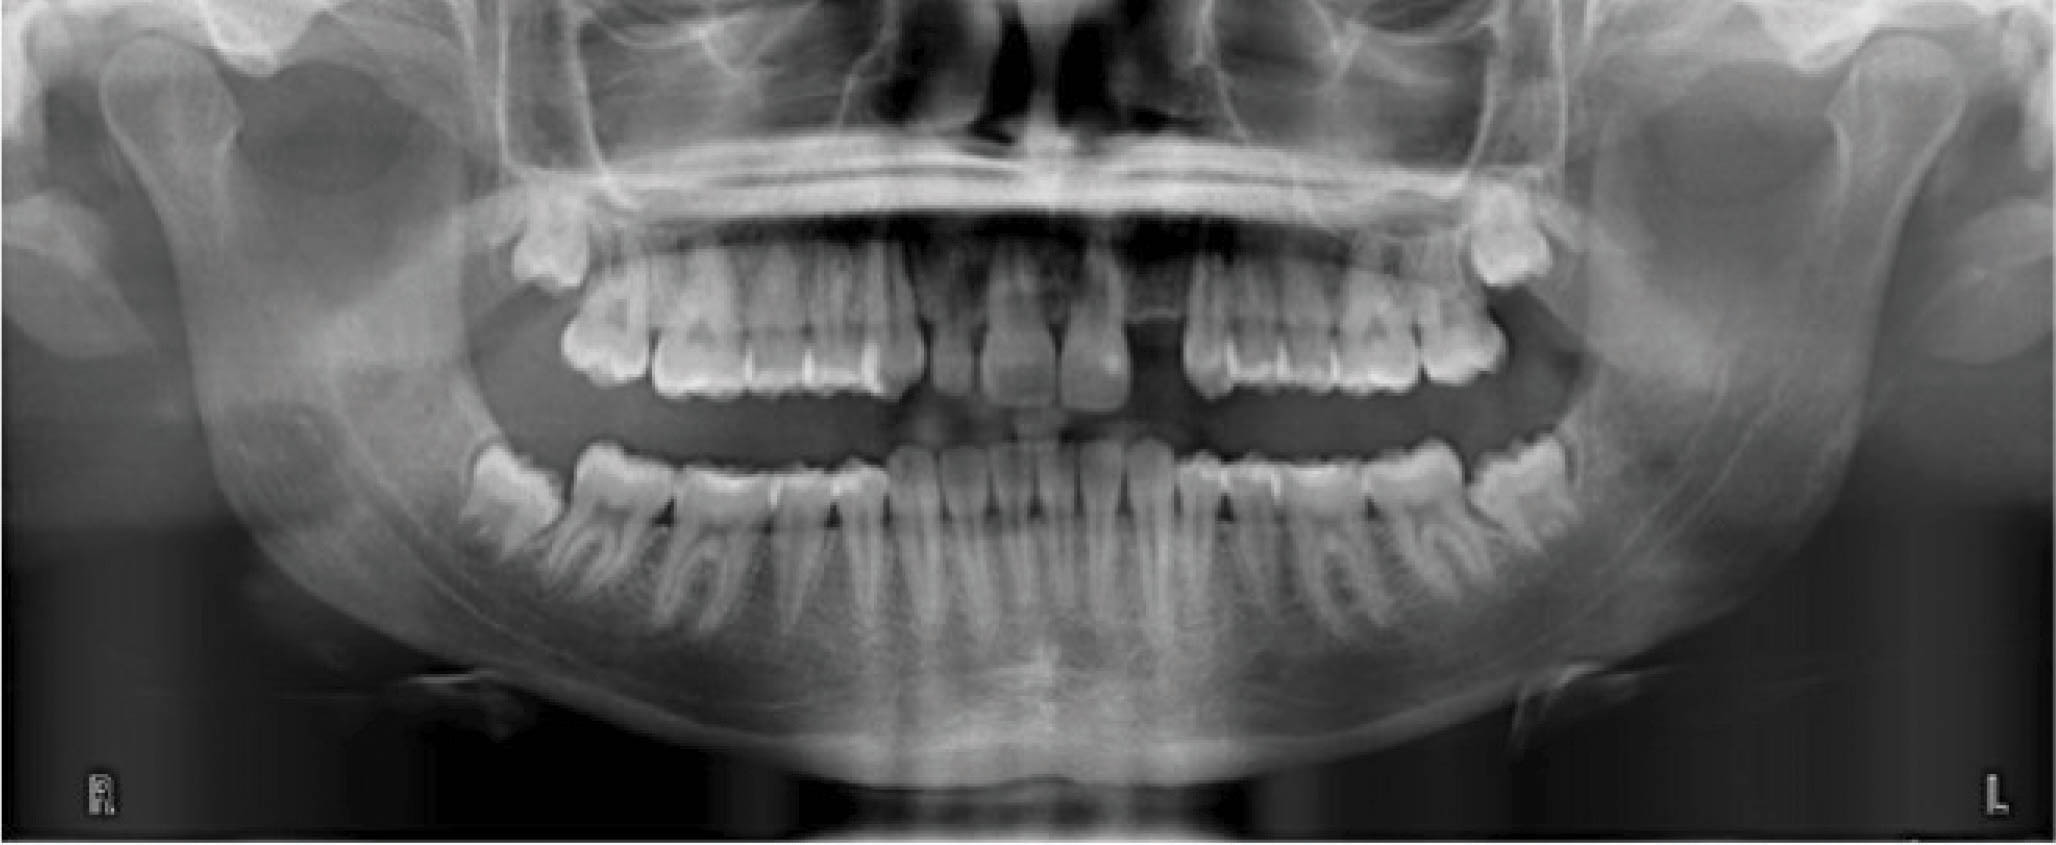

بیمار دیگر (شکلهای 50-6 الی 52-6): لترال چپ بالا را ندارد. هدف دیستاله نمودن کانین چپ بالا و هدایت آن تا رسیدن به رابطه کلاسI کانینی و نهایتاً قرار دادن یک ایمپلنت در ناحیه لترال است. اگر به OPG او نگاه بندازید، میبینید که لترال چپ بالا وجود ندارد و لترال راست بالا هم peg shape است.

: باید به لابراتوار بگوییم که تیپ دیستالی بیشتر به ریشه کانین چپ بالا بدهد. این زاویه بیشتر برای بیومکانیک کار است تا دندانها تیپ نشوند. باید در این بیمار هم همین کار را انجام داد. از آنجایی که قرار است کانین چپ بالا دیستالی بشود، احتمال دیستالی شدن تاج و مزیالی شدن ریشه وجود دارد. این حالت نه تنها مدنظر نیست، بلکه فضای کافی هم برای قرار دادن ایمپلنت به ما نمیدهد. بنابراین باید زاویه بیشتری به ریشه بدهیم تا در نهایت یک حرکت بادیلی داشته باشیم.

در OPG نهایی، کانین راست بالا در جایگاه صحیح است و فضا کافی برای ایمپلنت هم به وجود آمده است (کل درمان ۲۰ ماه به طول کشید). در این بیماران، باید حتماً درمان اضافه را در طراحی کامپیوتری در نظر بگیرید تا حرکتها بادیلی بشوند.